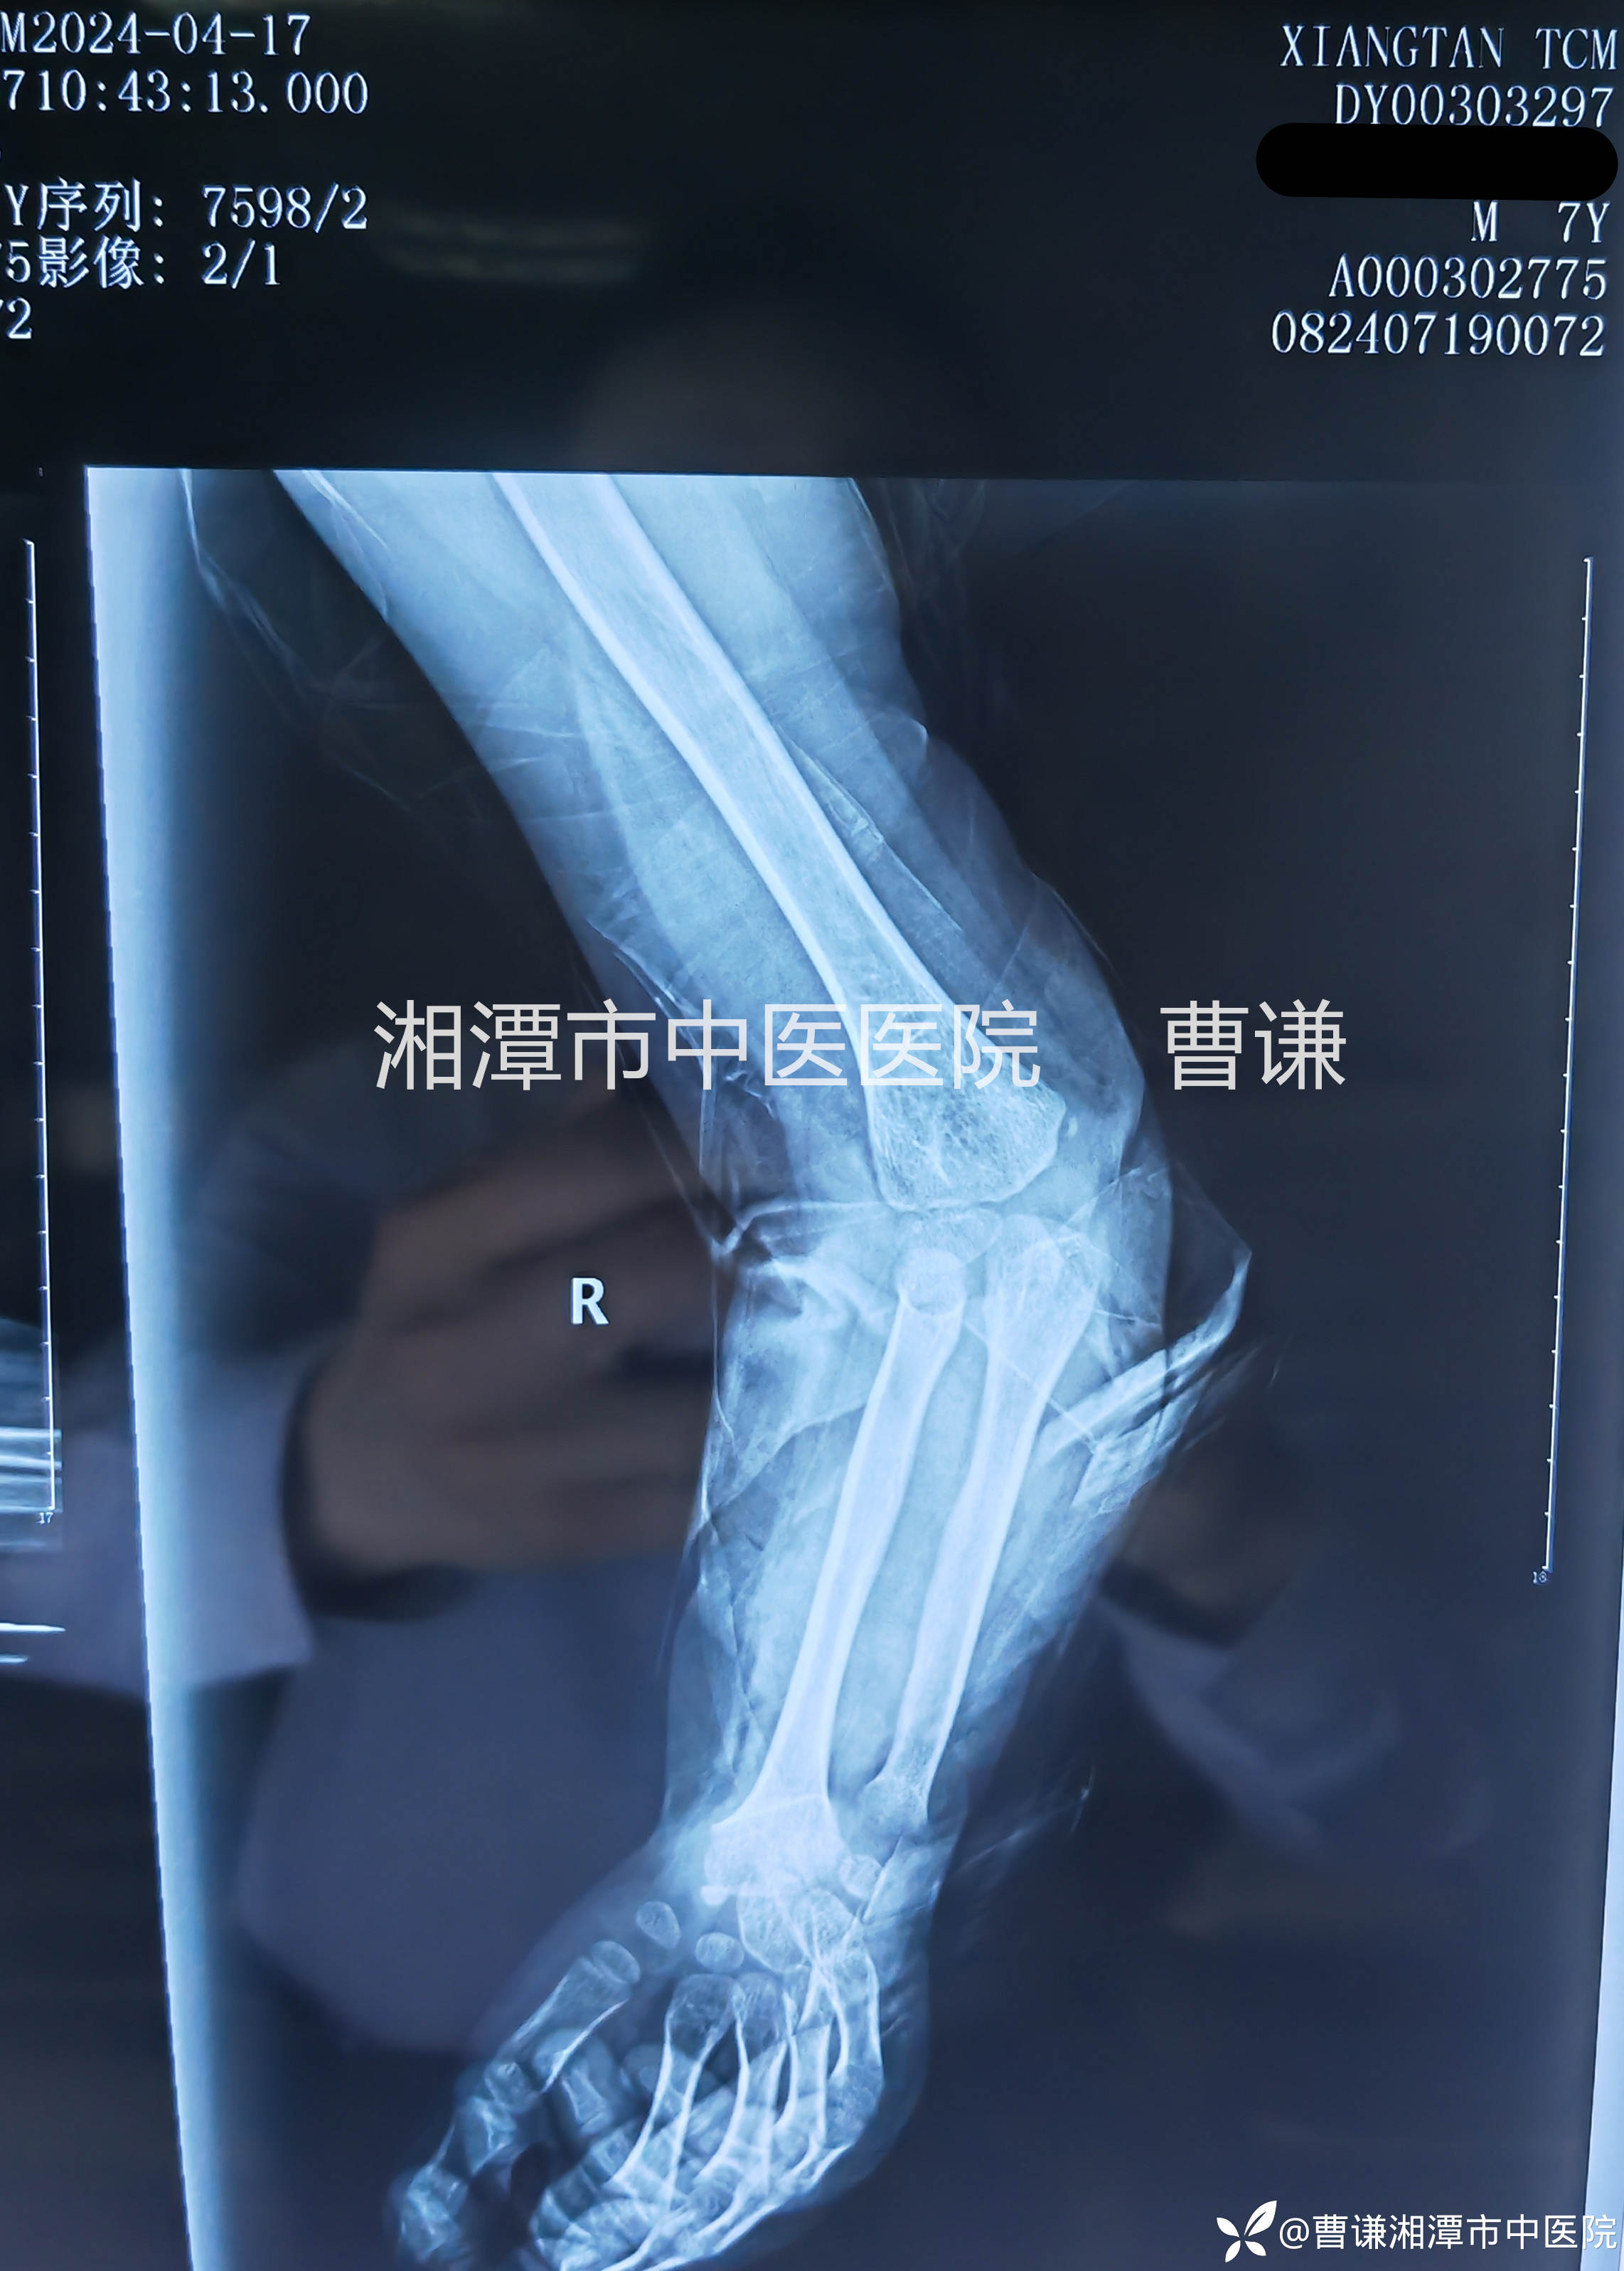

固定完成拍片复查示肱桡关节匹配良好。

伤后两周拍片复查未见明显异常,孩子就说一点都不痛了,小医生仔细体查局部无压痛,活动正常,主任指示拆除外固定,指导正常活动。